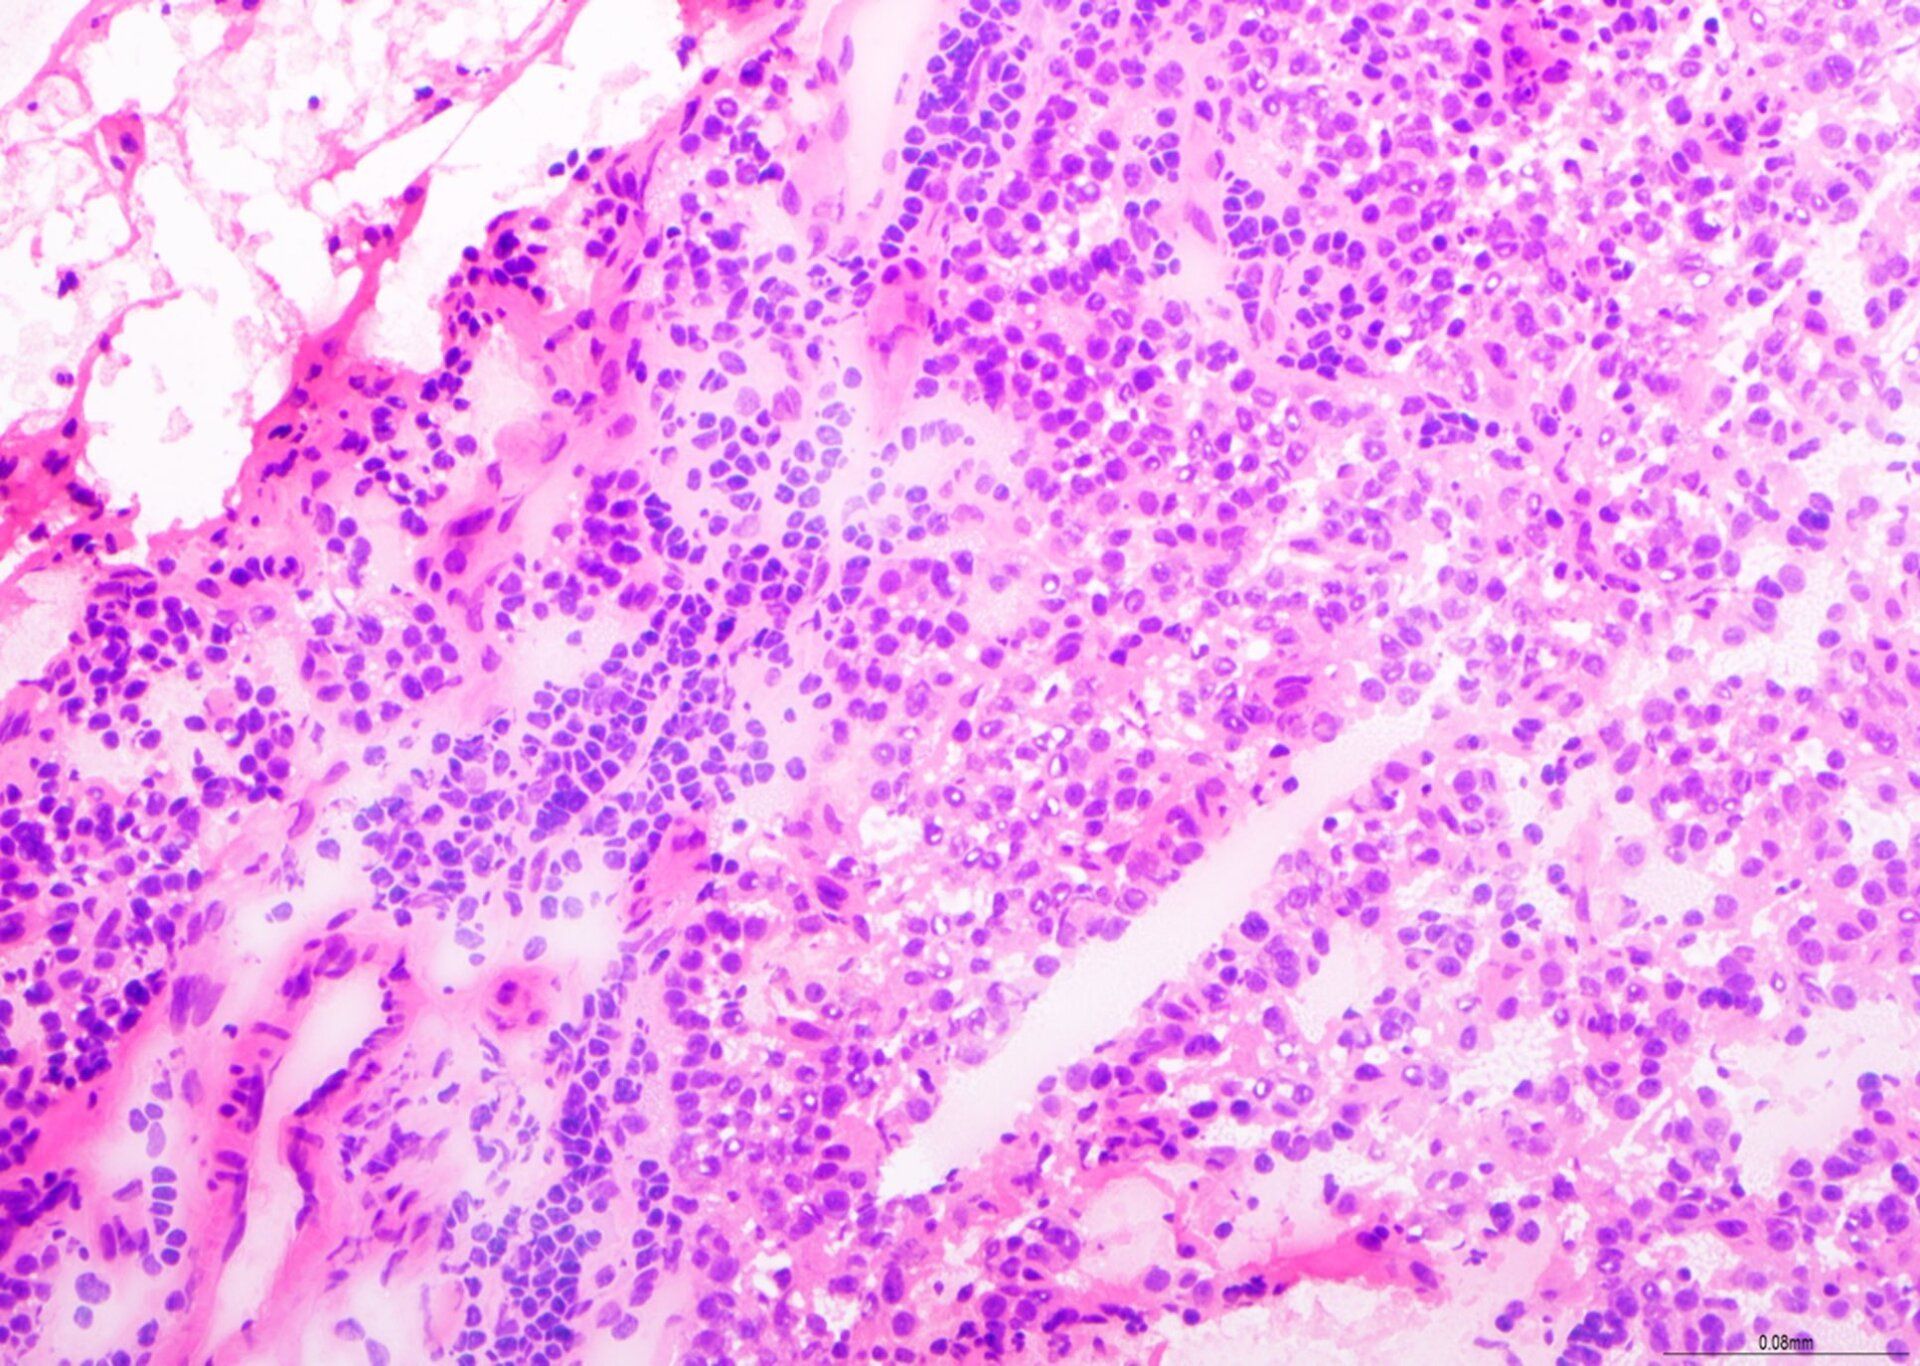

H&E - BMT Scheme

This is an excellent preparation of a BMT biopsy, with balanced H&E staining, good chromatin detail, and selective staining of cell types within the bone marrow tissue. This slide was scored 9/10 at assessment.